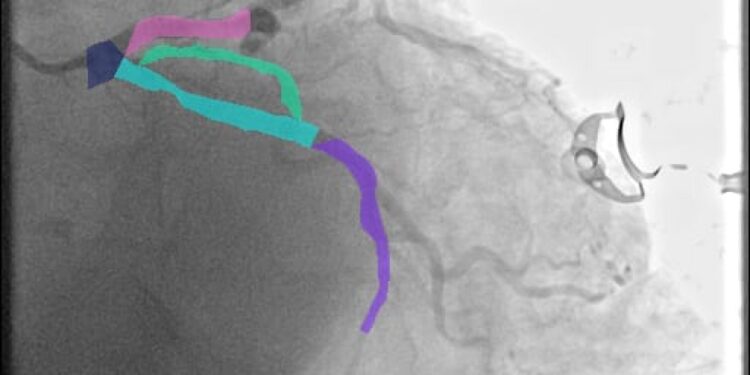

La investigación utilizó un conjunto de datos denominado ARCADE, generado en 2022 para un concurso internacional orientado al diagnóstico de problemas del corazón. A partir de esta base, se entrenaron modelos de aprendizaje profundo mediante la técnica YOLO (You Only Look Once), lo cual permitió segmentar imágenes en escala de grises para detectar con precisión tanto los vasos sanguíneos como las zonas críticas de estenosis.